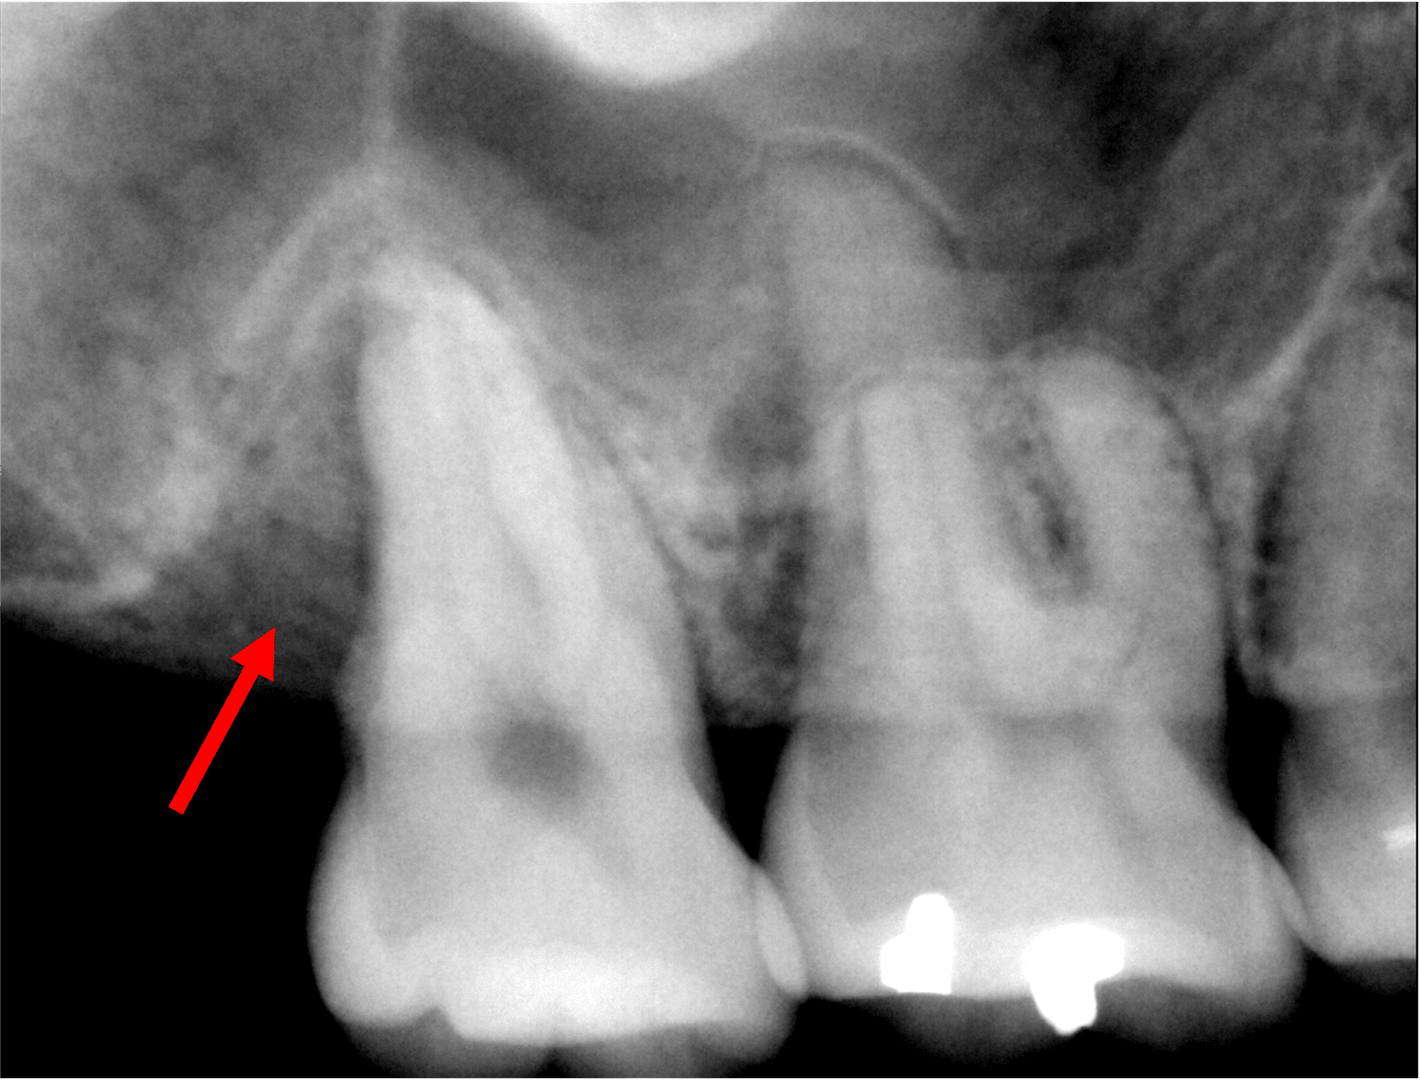

치주 재생 수술을 통한

치조골의 재생

치주 재생 수술을 이용한

치조골의 재생을 확인할 수 있습니다

치료 전

본 이미지는 촬영 조건에 따라 실물과 일부 다르게 보일 수 있으며, 환자 본인의 동의를 얻어 촬영 후 게재하였습니다.

치료 결과는 환자 개개인의 상태에 따라 다르며, 치과의사의 상담이 필요합니다.